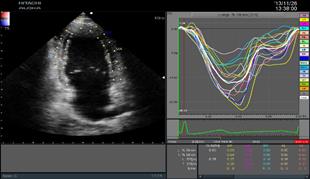

二維心肌組織追蹤2DTT

(2D Tissue Tracking)

ARIETTA 70-02模式匹配技術(shù)準(zhǔn)確識別并跟蹤感興趣的點(diǎn),智能化分析心肌節(jié)段運(yùn)動(dòng),準(zhǔn)確評估心肌局部運(yùn)動(dòng)功能及各節(jié)段運(yùn)動(dòng)的協(xié)調(diào)性,構(gòu)建左室“牛眼圖”,直觀顯示心室各段功能狀態(tài)。